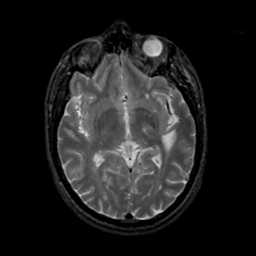

MR Study #19, August 25, 1991 -- Slice #24